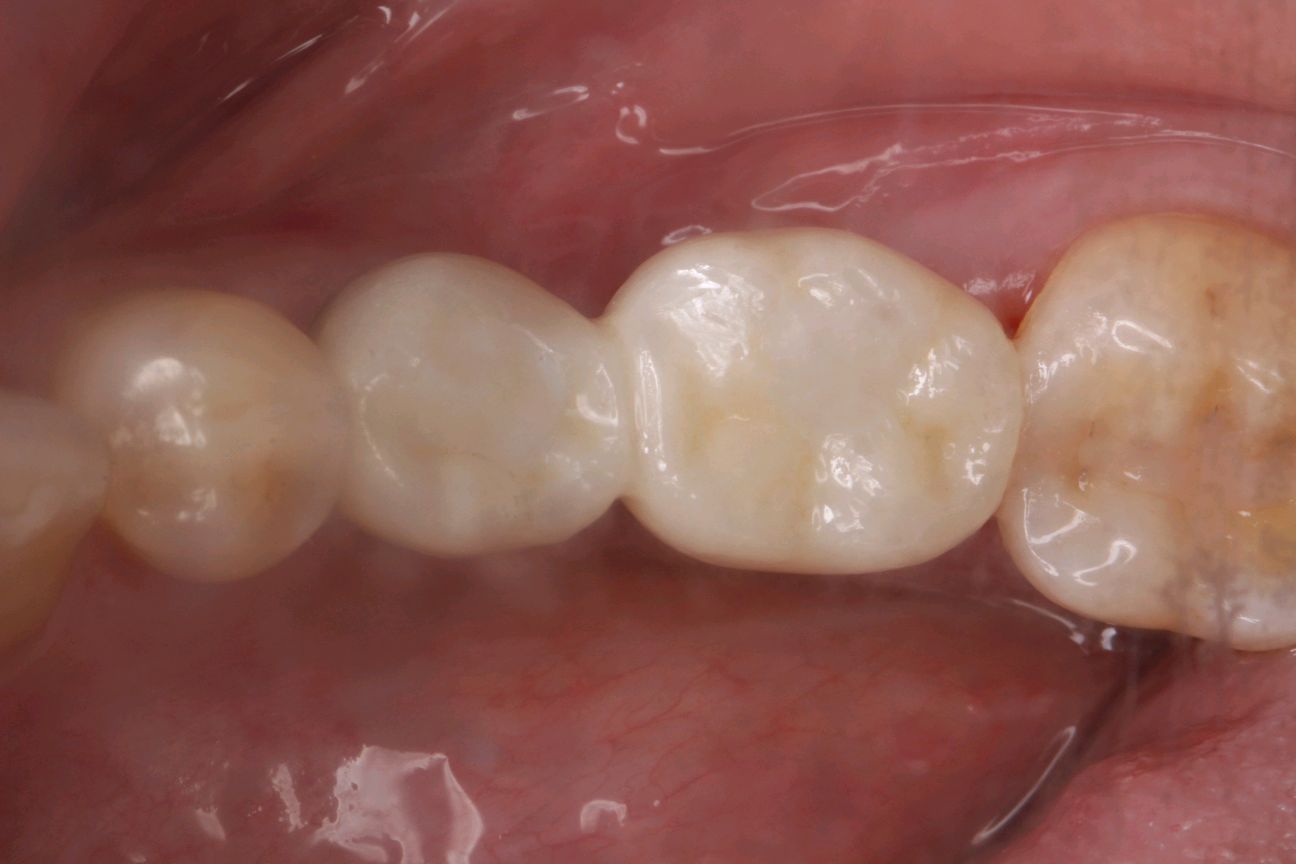

最终患者在做完牙周治疗后,拔除患牙。三月后植入ITI种植系统,植入骨粉骨膜及CGF膜严密缝合。术后骨结合良好。二期三期如期顺利进行,最终于今日安装牙冠,完成种植。患者满意。